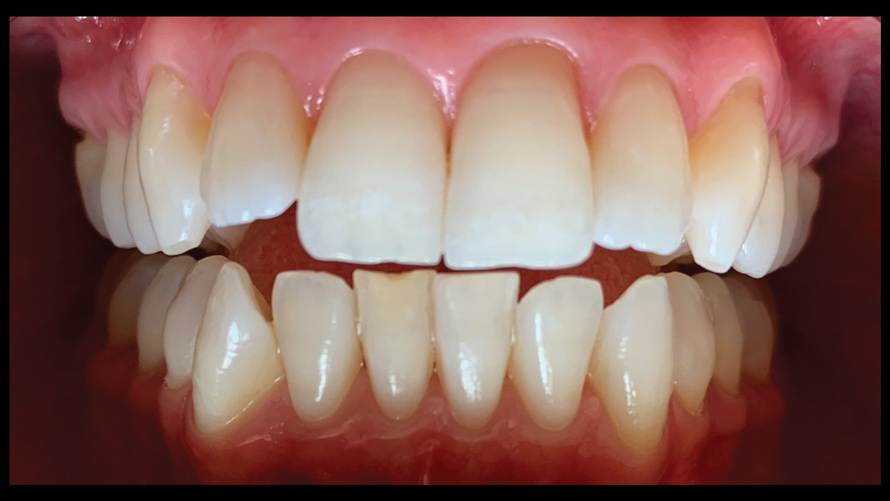

(9. through 11.) Preoperative esthetic case documentation using a smartphone and an EALS device.

Figure 9

Figure 10

Figure 11